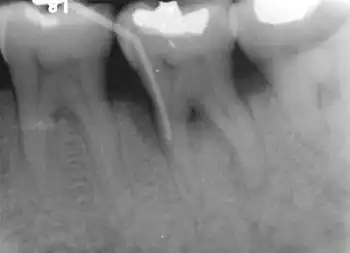

Furcation defect

In dentistry, a furcation defect is bone loss, usually a result of periodontal disease, affecting the base of the root trunk of a tooth where two or more roots meet (bifurcation or trifurcation). The extent and configuration of the defect are factors in both diagnosis and treatment planning.[1]

Diagnosis

Nabers probe is used to check for furcation involvement clinically. Recently, cone beam computerised technology (CBCT) has also be used to detect furcation.[5] Periapical and interproximal intraoral radiographs can help diagnosing and locating the furcation.